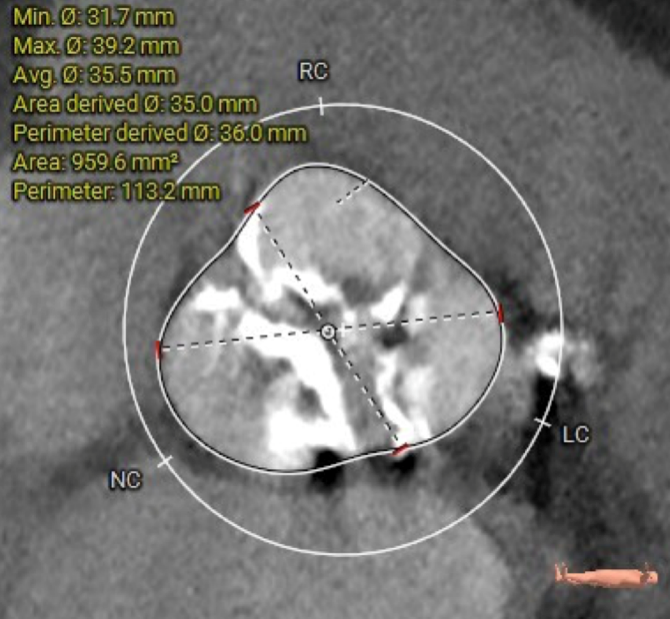

CT数据显示该患者为type1型主动脉瓣。

主动脉瓣瓣环周长75.2mm,平均周长径 23.9mm,SOV:34.7mm*33.8mm*32.9mm,瓣叶增厚,瓣上钙化分布不均,瓣环水平夹角58°。

冠脉高度测量

LEFT CORONARY

左冠开口高度14.0mm

RIGHT CORONARY

右冠开口高度13.1mm

钙化分布